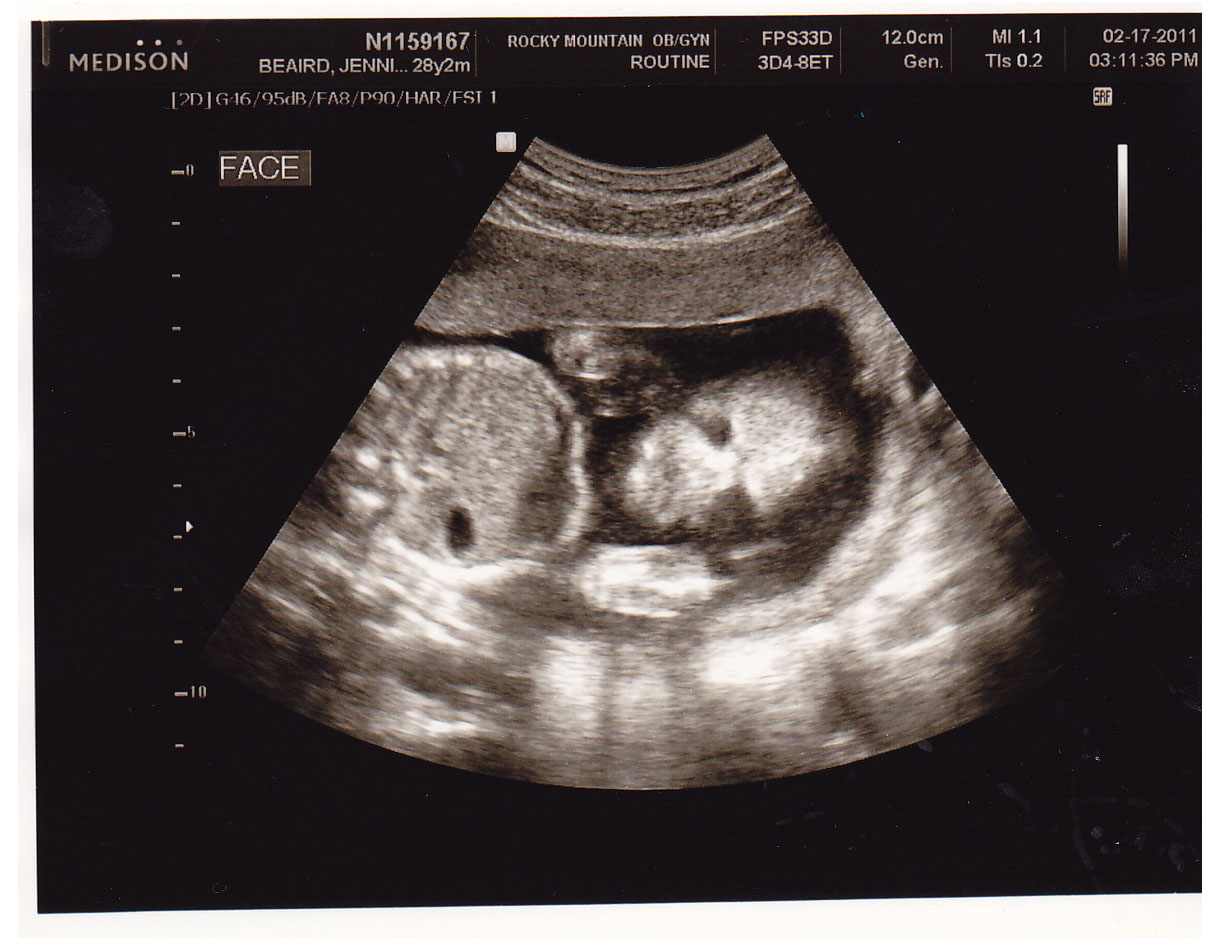

Face shot, a little freaky, but cool too.

You can see that she's giving a thumbs up right by her face.